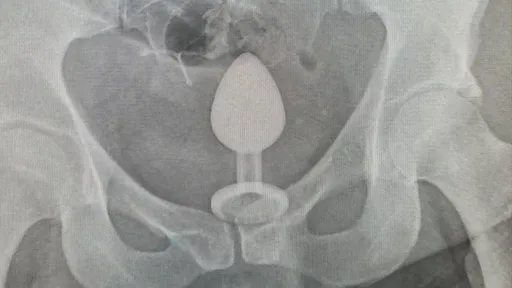

...功,她開始感到害怕,並到醫院求助。 一名醫師戴上橡膠手套後,在查普曼肛門附近塗了潤滑油,然後緩緩地...